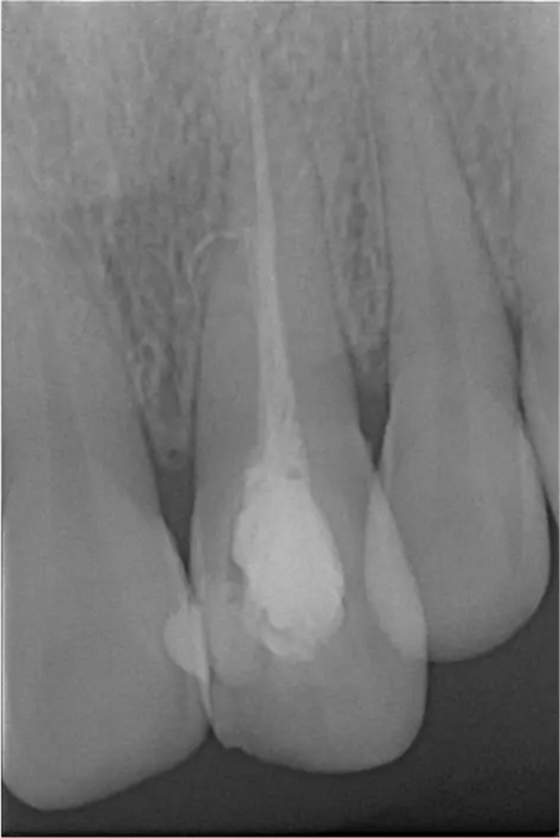

患者女,年齡35左右,牙位21,根管治療曾經(jīng)歷過(guò)外院四到五次等不同地方的處理,還是不能咬硬物,會(huì)有酸、軟、痛的情況出現(xiàn),偶有自發(fā)疼痛,2016年9月初,轉(zhuǎn)診至我處治療21。術(shù)前拍片發(fā)現(xiàn)根中部存在側(cè)穿,橡皮障下常規(guī)再治療,隨后減輕了軟和痛的情況。因?yàn)閭?cè)穿,牙周膜受到牙膠尖等異物的持續(xù)刺激,酸軟的情況還是持續(xù)存在,所以決定行根尖外科手術(shù),采用MTA修補(bǔ)穿孔點(diǎn)。術(shù)后觀察半年左右,所有癥狀消除后,隨后熱牙膠充填。

術(shù)前診斷片